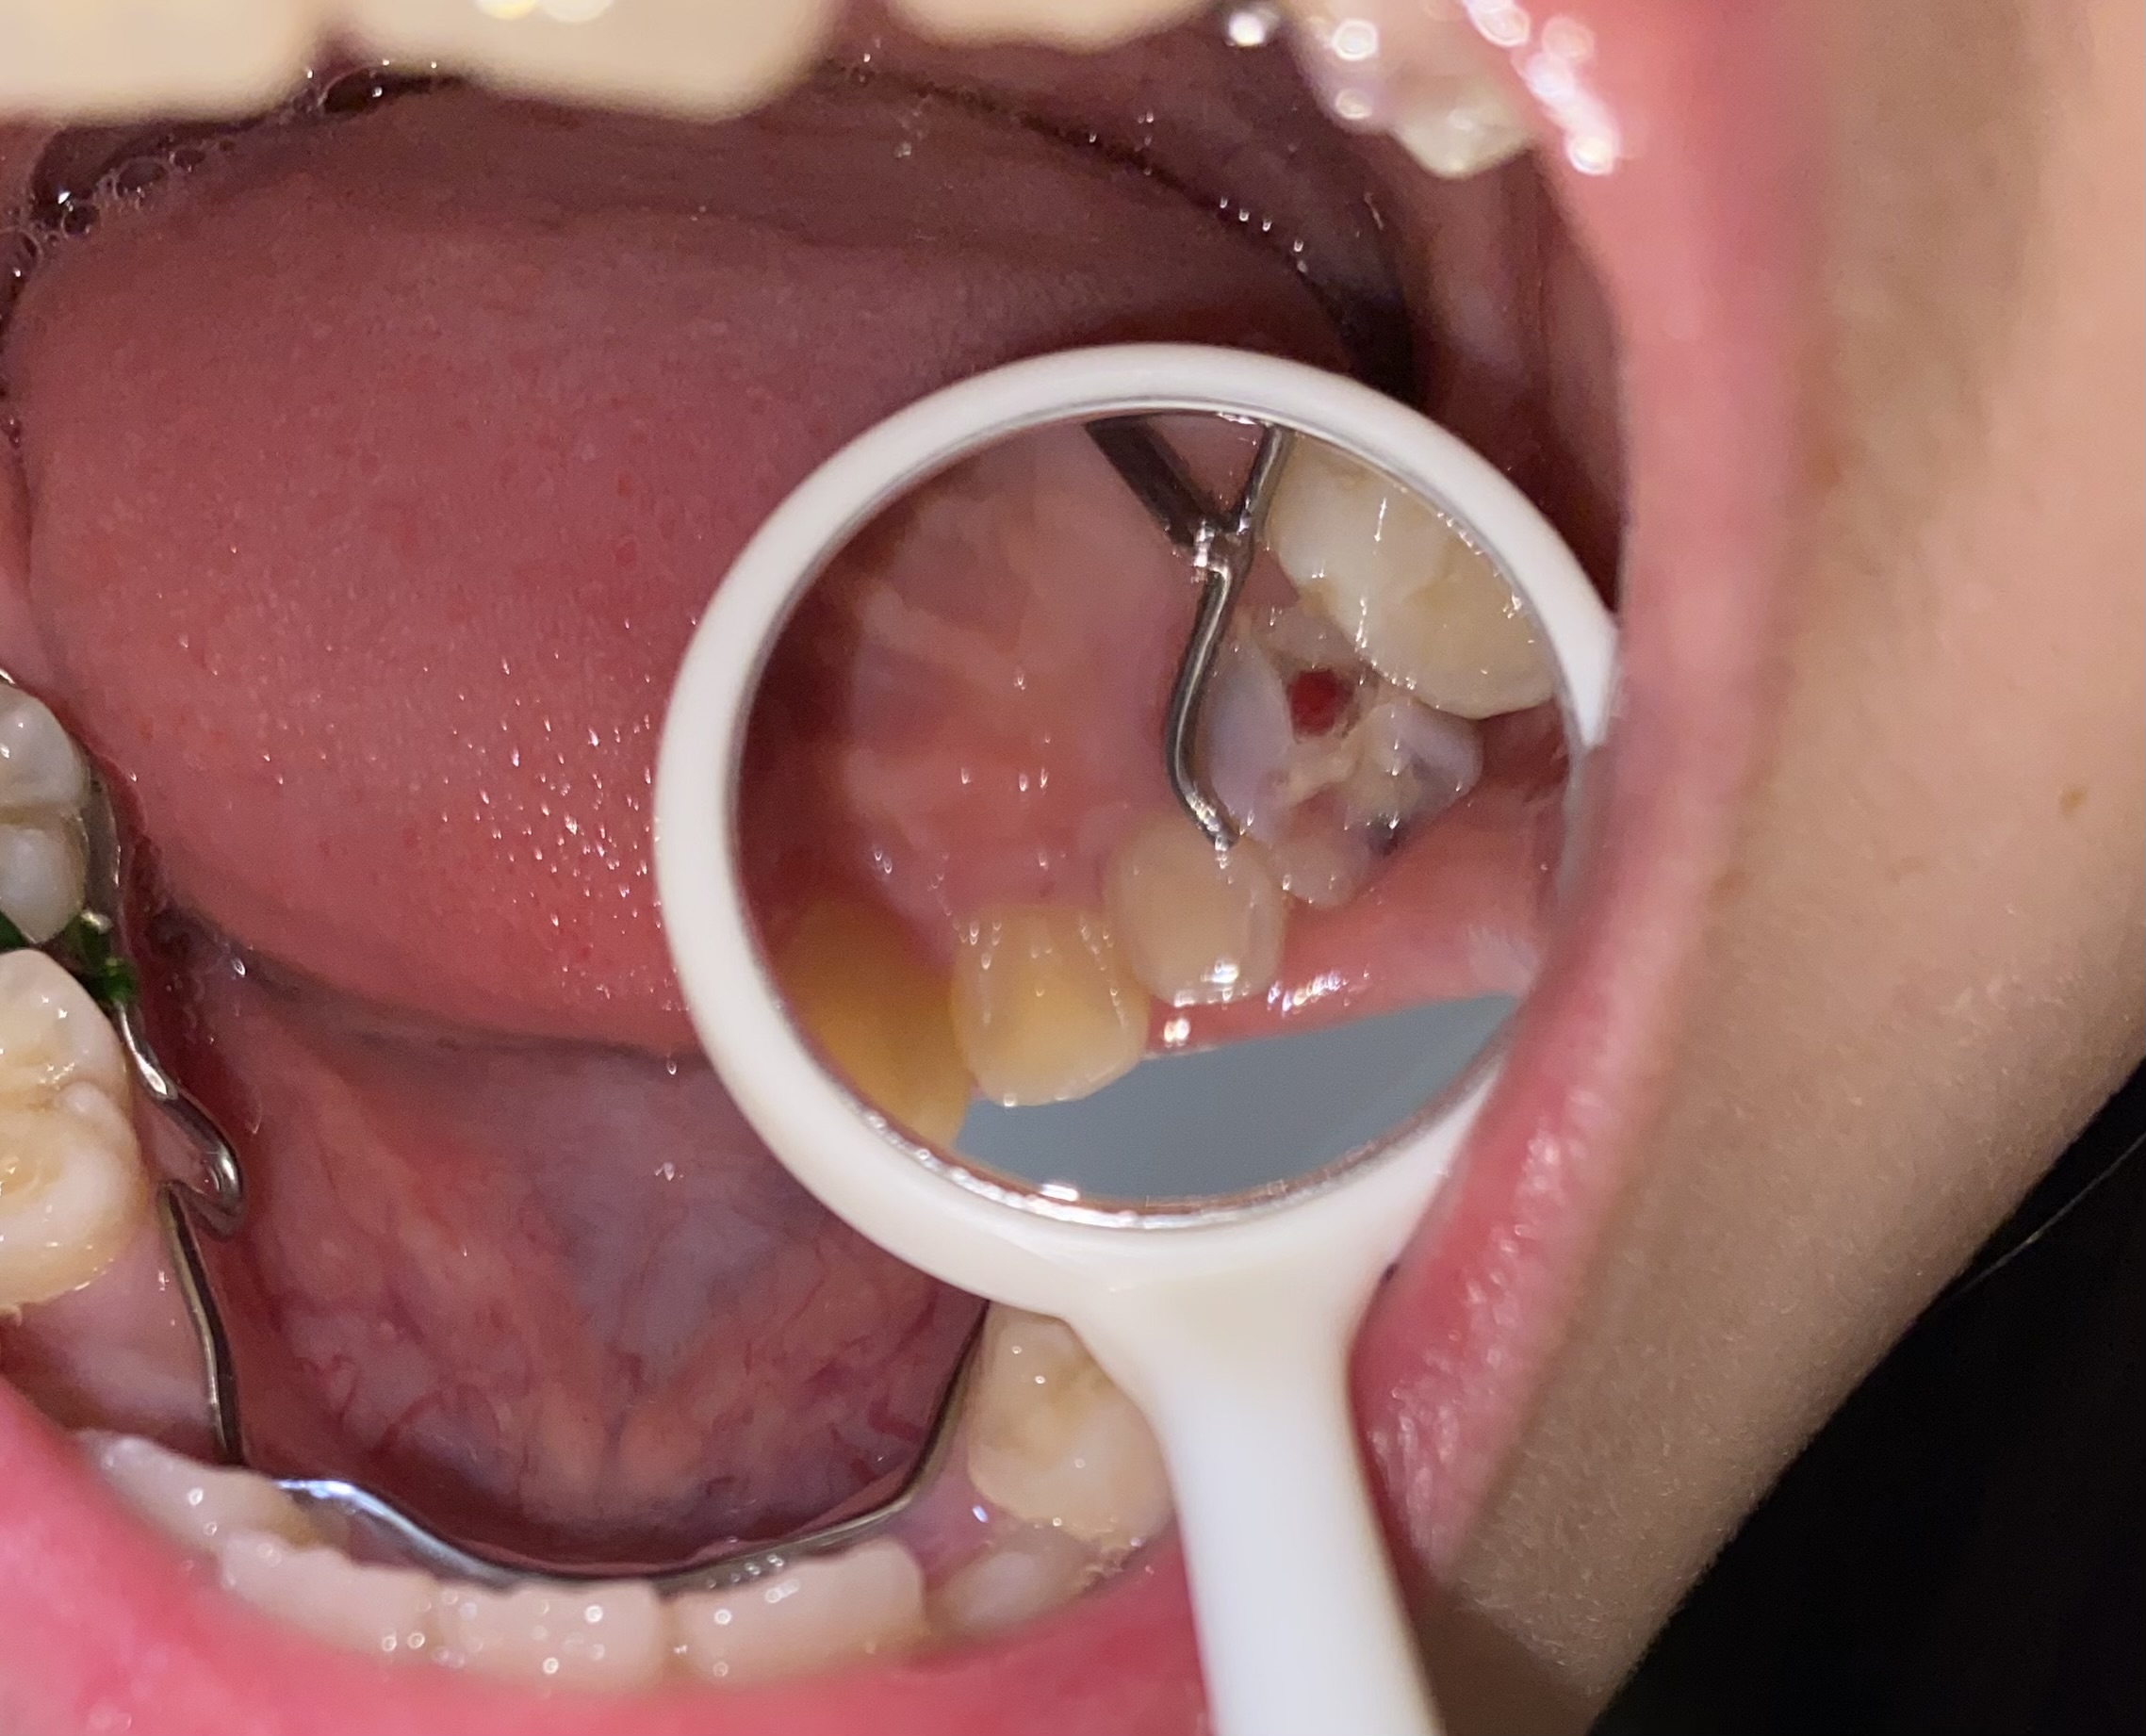

10歳の娘が歯科矯正中でブラケットをつける前の段階で上顎を広げるエクスパンダーを装着中です。あと7回きつくする必要があるとのことで今日5回目の穴に針金のようなものを入れて回す作業をする予定でしたが、元々グラグラだった乳歯が日中にかけてしまいました。昼間にヒビが入っていることに気がついたらしいのですがその話をしている最中に触っていたら少しかけました。

エクスパンダーに接しているのですが、このまま回す作業をしても大丈夫でしょうか?

もしかしてこの器具のせいで負荷がかかり 歯が欠けたのでしょうか?

なおエクスパンダーに接しているために抜けにくいと言うことはありますか?

画像1IMG_7611.jpeg